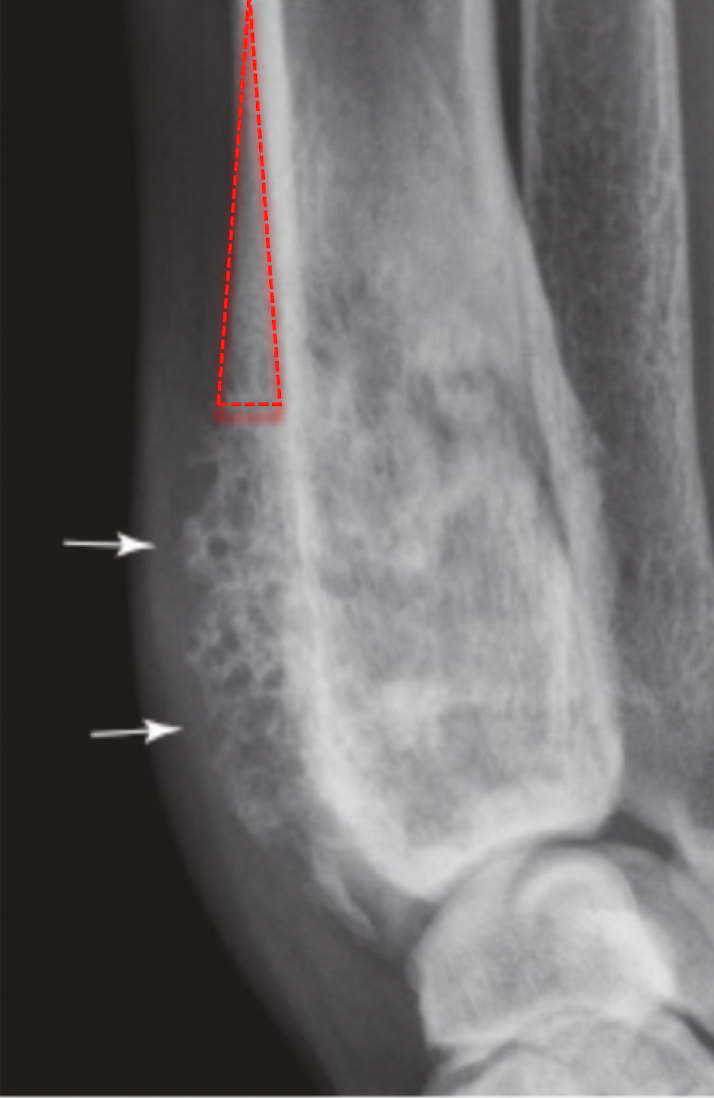

xray of OSA will show

A

cortical destruction

lysis- moth eaten or permeative

periosteal proliferation: codman’s triangle

medium to long zone of transition

rarely crosses joint